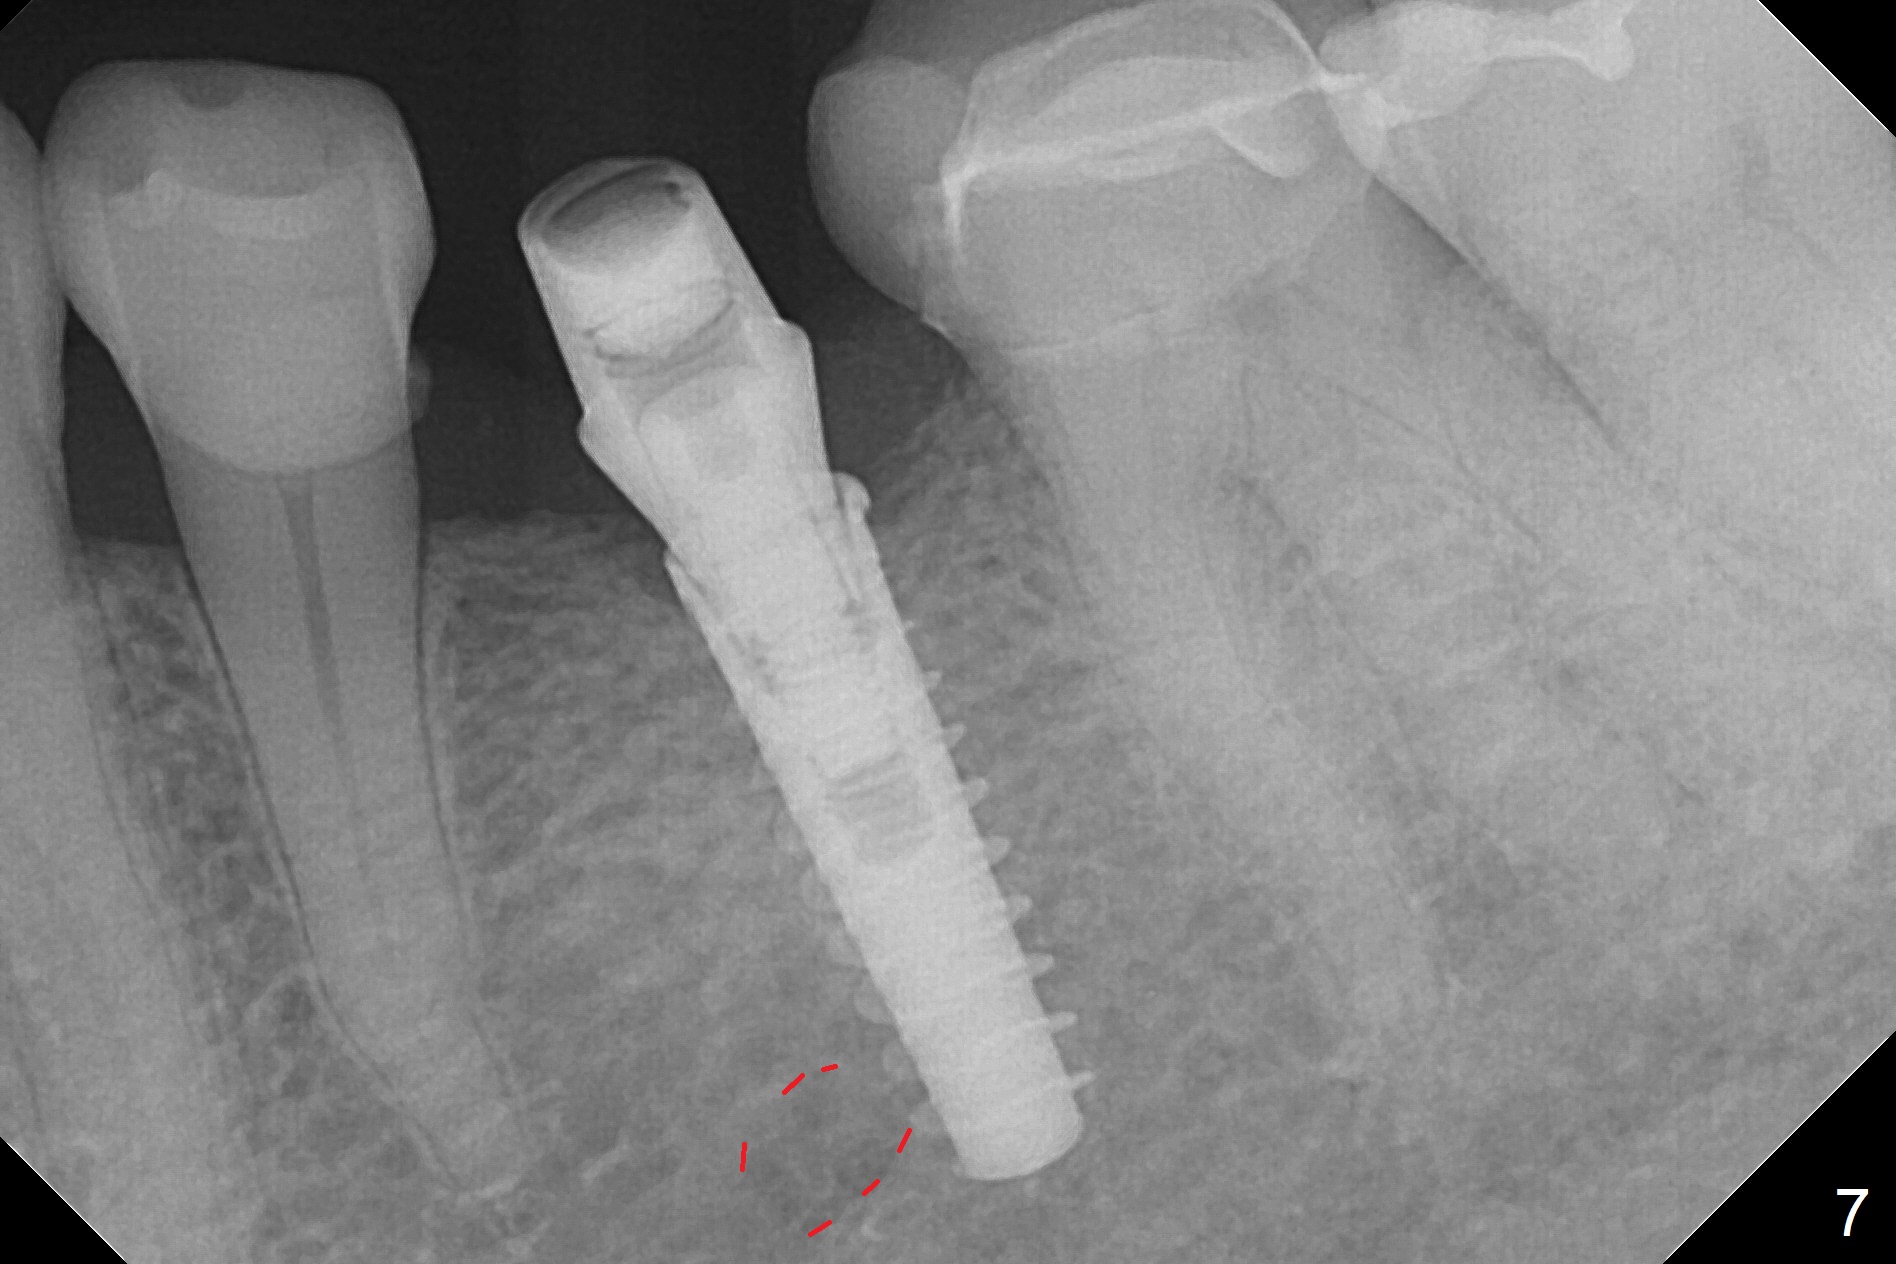

Initial osteotomy with 1.6 mm drill for 11 mm seems to be distal (Fig.1).  The trajectory should be changed as shown by the black line in Fig.2; the drawback would be close to the Mental Loop (red line).  Fortunately the trajectory is changed, but not so much as to be close the Loop when a 4x11 mm dummy implant is placed (Fig.3).   When a 4x13 mm IBS is placed with 46 Ncm, there is clearance from the Loop (Fig.4-6).  In fact there is no postop paresthesia.  The main point is no block anesthesia.  Infiltration anesthesia is administered with 34 mg Xylocaine with 17 mcg Epinephrine.  The patient experiences dull pain when the implant is placed (Fig.4-6).  After further anesthesia with 68 mg Septocaine, 17 mcg Epinephrine, the implant is torqued for a few turns (still with some discomfort).  Finally autogenous bone with Osteogen is placed around the implant following placement of a 4.5x4(2) mm abutment.  To reduce anxiety, a shorter implant should have been used. The patient complains of cold sensitivity in the lower left quadrant 4 months postop (Fig.7): the implant apparently close to the Mental Loop.  Without an immediate provisional, the gingiva around the abutment is healthy.